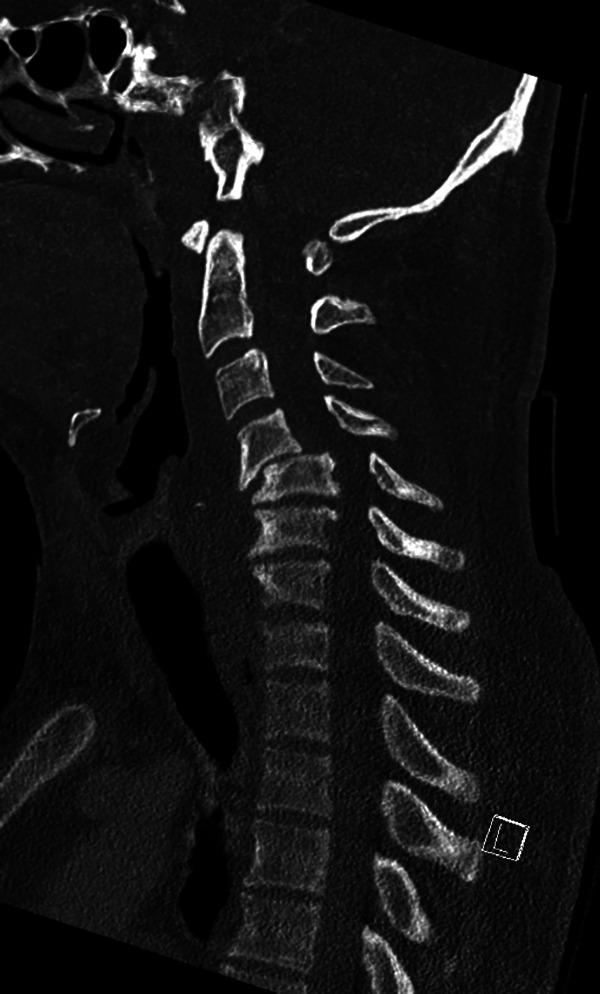

Spinal Cord Injury With Tetraplegia in Young Persons After Diving Into Shallow Water: What Has Changed in the Past 10 to 15 Years?

To analyze prehospital and clinical findings, complications, neurological improvement and follow-up in a young person cohort with spinal cord injury (SCI) and tetraplegia according to the American Spinal Injury Association (ASIA) Impairment Scale (AIS) A to D after diving into shallow water.

Included were all persons younger than 50 years with SCI after head-first diving into shallow water between June 2001 and June 2019. All persons with SCI were divided into complete tetraplegia (AIS A) and incomplete tetraplegia (AIS B, C, and D) to test differences.

A total of 59 males (98.7%) and 1 female with a mean age of 27.7 years suffered an SCI. Alcohol use was documented in 25 cases (41.7%). At the time of admission, 33 people (55%) showed a complete tetraplegia (AIS A) and 27 showed an incomplete tetraplegia with 8 AIS B (13.3%), 15 AIS C (25%), and 4 AIS D (6.7%). At the time of discharge, people with initially complete tetraplegia showed a significant improvement from admission to discharge ( ≤ .004). Persons with incomplete tetraplegia were more likely to improve their neurological status compared with complete tetraplegia patients ( ≤ .001). Especially persons with complete tetraplegia suffered from typical SCI-related problems and complications.

People with SCI and tetraplegia at the time admission show neurological improvement in 50% of the cases with an overall better outcome in persons with incomplete tetraplegia. The surgical treatment of SCI within 24 hours seems to be associated with a better neurological outcome and a lower level of tetraplegia. The incidence of SCI caused by diving into shallow water remains stable without a significant change, especially in high-risk groups. More education and prevention programs are necessary to avoid these injuries.